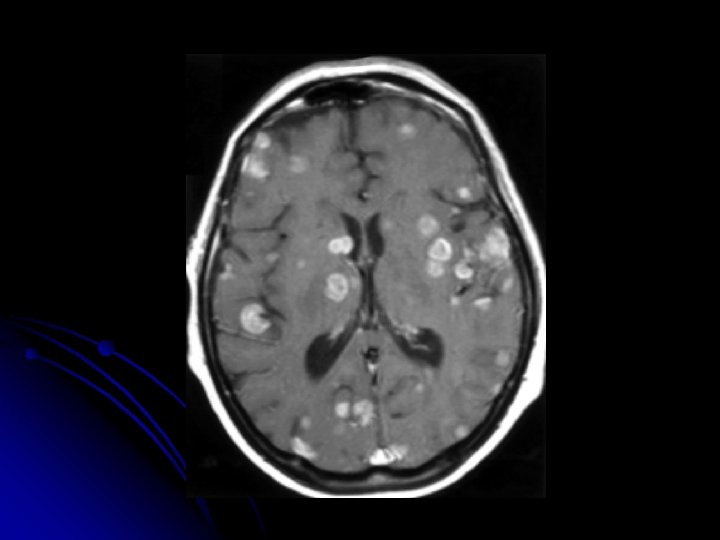

NEUROIMAGING OF METASTATIC BRAIN DISEASE o Contrast CT scans are often the initial imaging modality for symptomatic patients with unknown brain metastases. o On MRI , most show mild T 1 hypointensity with T 2 hyperintensity and FLAIR hyperintensity. o Metastases tend to be most commonly located in the supratentorial compartement with the exception of those from renal cell carcinoma that tend to be infratentorial.

MRI AND CT l On MRI, mild T 1 hypointensity with T 2 hyperintensity and FLAIR hyperintensity. l Hemorrhagic metastases demonstrate hyperdensity on NCCT and T 1 hyperintensity on noncontrast MRI. l Metastases from malignant melanoma may demonstrate T 1 hyperintensity because of hemorrhage or melanin components.

MRI T 2 AND CONTRAST